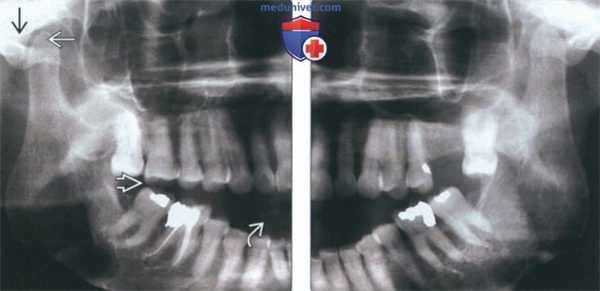

(Слева) На панорамной рентгенограмме у пациента с двухлоронним передним вывихом визуализируется правый мыщелок, смещенный кпереди и кверху относительно сулавного возвышения. Обратите внимание на явный передний открытый прикус, в то время как моляры находятся в окклюзии.

(Справа) На панорамной рентгенограмме у этого же пациента определяются аналогичные изменения слева. Открытый прикус обусловлен неправильным передним положением мыщелка, контакт задних зубов - его верхним положением.

(Слева) На рентгенограмме в боковой проекции у этого же пациента определяется прогнатическое положение нижней челюсти и открытый передний прикус вследлвие передне-верхнего смещения мыщелков нижней челюсти.

(Справа) На сагиттальной КЛКТ правого и левого мыщелков у этого же пациента определяется, что мыщелки расположены спереди и сверху относительно сулавных возвышений. Обратите внимание, что мыщелки имеют нормальную форму, а кортикальная плалинка не изменена.